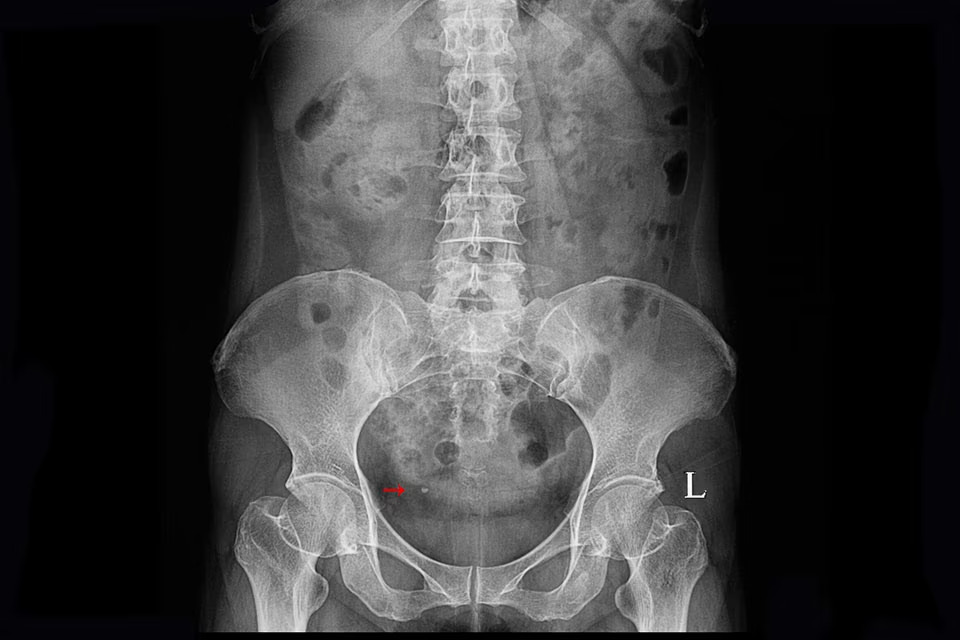

Les causes les plus fréquentes sont variées. Les infections urinaires sont responsables

d’une irritation des muqueuses pouvant entraîner un saignement. Les calculs urinaires, en

migrant dans les voies excrétrices, provoquent des lésions mécaniques. Les traumatismes

Uroscanner

L’uroscanner (ou uro-TDM) est l’examen de référence en cas d’hématurie macroscopique

inexpliquée, surtout chez les patients à risque. Réalisé avec injection de produit de

contraste, il offre une analyse complète de l’appareil urinaire, du parenchyme rénal jusqu’à la

vessie. Il est particulièrement performant pour détecter des tumeurs urothéliales, des calculs

ou des malformations anatomiques.